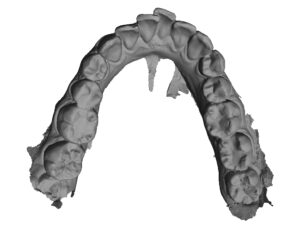

Analizę przemieszczeń zębów w zakresie mezjalizacji trzonowców w szczęce oraz przemieszczenie przedtrzonowca górnego rozpoczęto dopiero po uzupełnieniu zlecenia o analizę zdjęcia panoramicznego oraz badań dodatkowych. Opisano trzy opcje leczenia tego pacjenta. Pierwsza propozycja obejmowała brak mezjalizacji d. 26 i d.27; dystalizację w zakresie wybranych zębów. Druga propozycja obejmowała minimalną dystalizację drugiej ćwiartki łuku zębowego. Trzecia propozycja obejmowała sekwencyjną mezjalizację d. 26 oraz d. 27.

Cyfrowy plan leczenia przeanalizowano pod kątem osiągnięcia klinicznego celu zaplanowanego przez lekarza. Zaplanowana na cyfrowym planie leczenia mezjalizacja nie uwzględniała rekomendowanego sekwencyjnego przemieszczania zębów. Oznaczało to bardzo mało prawdopodobne zajście tych ruchów w jamie ustnej u pacjenta. Opisano lekarzowi, na czym polega sekwencyjna mezjalizacja zębów i jak zaprojektować ją w nowym planie leczenia. Zwrócono uwagę, że tego typu przemieszczenia zębów są bardzo wymagające, dlatego lekarze do zwiększenia możliwości ich zajścia stosują np. miniimplanty ortodontyczne. Opisano wpływ ilości i jakości attachmentów na zwiększenie przewidywalności ruchów zębowych.